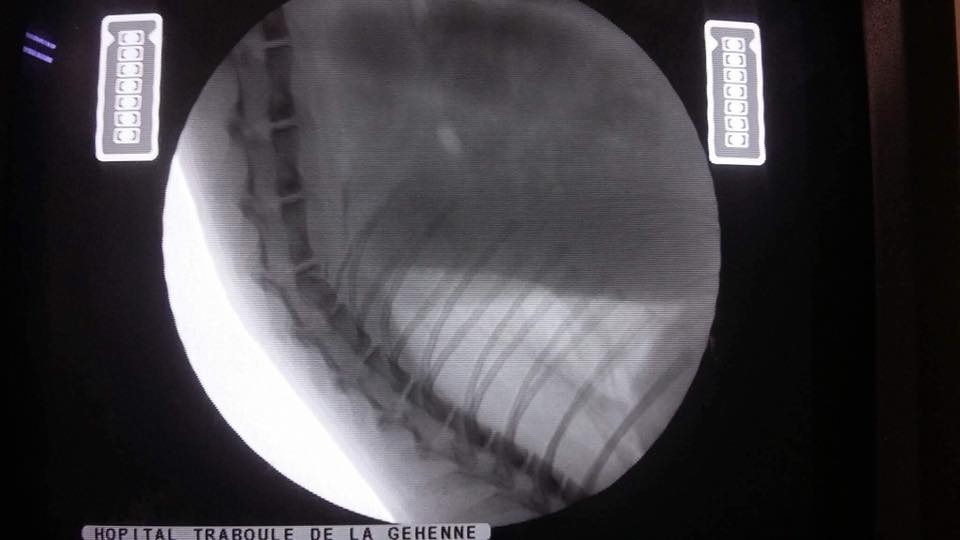

Bác sĩ ở đây nói Dũng đưa mèo qua trung tâm khác để chụp X-quang. Chàng trai ngồi khóc sau khi nhận kết quả Xù bị tách xương hàm, rạn xương chân trước, gãy xương đòn chân sau, hỏng xương cột sống ảnh hưởng dây thần kinh, liệt nửa người bên dưới... kèm với đó là cái lắc đầu của bác sĩ.

![]() ![]() ![]() ![]() ![]() |

| Các hình ảnh chụp X-quang của chú mèo Xù được Dũng cung cấp. Ảnh: NVCC. |